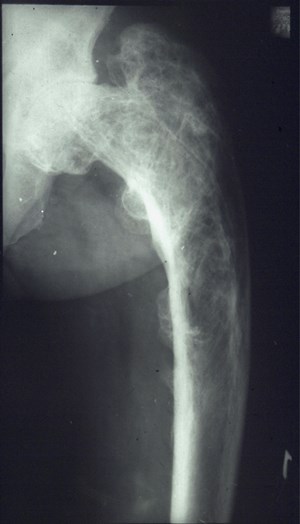

Патологические гипертрофические явления в кости, или так называемый гиперостоз, возникает в результате различных патологических явлений, при которых утолщается костная ткань за счет ширины надкостницы, называемой пероистом. Следовательно, процесс увеличения ширины периоста называется периостозом.

Гиперостоз является в основном вторичным проявлением. Этиологией его выступает воспалительный процесс, травматические дефекты, расстройство гормонального фона, хронические интоксикации веществами, содержащими мышьяк или фосфор, и пр. Первичный же гиперостоз происходит при наличии в организме патологического состояния как врожденный гигантизм.

Гипертрофические явления в скелете возникают у легкоатлетов, спортивных игроков, гимнастов и прыгунов в воду в тазовой зоне таза в виде незначительного трансформации вертлюжной впадины. Дискометатели имеют утолщение дистального конца диафизарной части бедренной кости. У бегунов возникает повышенное расширение большеберцовой кости в зоне бугристости и малоберцовой – в головочной зоне. Гипертрофия хоккеистов и борцов характеризуется увеличением ширины проксимальных эпифизарных частей костных структур голени. Выраженному трансформированию подвергаются позвоночные сегменты, позвонки становятся четырехугольной либо клиновидной формы. Первая отмечается в основном у пловцов. Вторая характеризуется клином, который суживается кпереди, свойственна для штангистов, гребцов и велосипедистов, а клином, который суживается кзади, — для борцов.